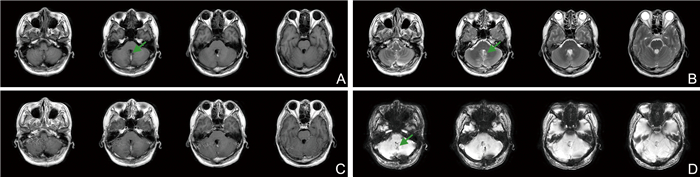

小脑认知情感综合征1例报告并文献复习

姚红艳, 唐莲, 王倩, 张玉梅

2026, 24(2): 350-353. doi: 10.16766/j.cnki.issn.1674-4152.004395

6 0

摘要:

临床上小脑损伤患者会出现认知功能障碍及情感调节障碍,临床表现轻于大脑受损所致的认知障碍,在实际工作中易被忽略。本文报道1例血管母细胞瘤患者因出现小脑或其环路受损导致出现轻度认知功能障碍及情感调节障碍的病例,患者男性,43岁,因“行走不稳3个月、反应减慢、焦虑、视物异常1.5个月”入院,入院后完善认知心理学测评等相关检查,最终诊断为“很可能的小脑认知情感综合征”;经过个体化的功能康复,患者症状均较前改善。本文对该病例进行报道,以期为临床上小脑认知情感综合征的诊断及治疗提供参考。